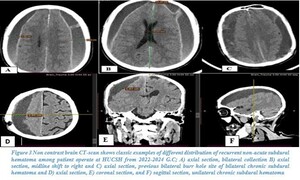

Headache (40.1%) and body weakness (33.3%) were the most common presenting symptoms. Older patients frequently presented with severe headaches and altered mentation, whereas younger individuals commonly exhibited variable body weakness and abnormal body movement. A trauma history was reported in 89.4% of cases, with most patients often suffering from simple falls (51%; Figure 1). In 81.4% of patients, the trauma occurred within 2 months prior to presentation. Most patients had an initial Glasgow Coma Scale (GCS) score of 15/15 (62.7%; see Table 2).

Radiological characteristics of NASDH patients at HUCSH

CT scan was the primary imaging modality used (87.6%). An iso-dense subdural hematoma was the most common radiological finding (54.7%), followed by a hypo-dense hematoma (42.9%). Most hematomas were unilateral (71.4%) with a left-sided predominance (41%). Most hematomas measured more than 2 cm in thickness (70.2%), and 59% demonstrated a midline shift of 5–10 mm (see Figures 2–4).